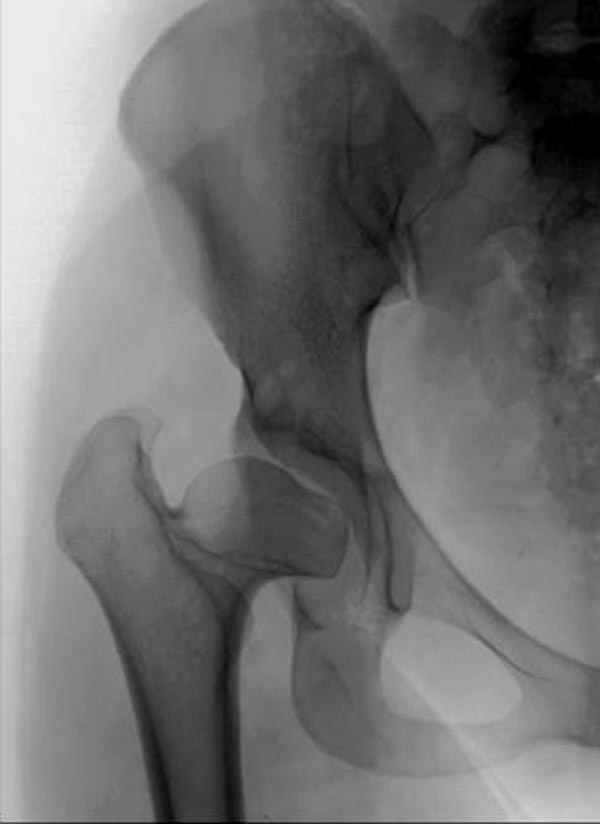

Dear All,This 27 year old presented to a colleague, about 2 years back, with complaints of bilateral hip pain. He was treated symptomatically, but now has increasing pain, and walking distance is being limited.

On examination, he has got a lordotic gait, Trendelenberg negative, bilaterally, hip movements fairly good, with no FFD.X-rays are attached.Kindly give your opinions regarding management and future prognosis.Thanks and regardsMuhammad Amin Chinoy FRCS

It appears that this patient has bilateral congenital hip displasia, as presented on the radiographs. As shown, the problem involves both sides of the hip joint: the acetabulum and proximal femur.

This patient is noted to have a very vertical joint surface orientation, as well, with retroversion of the acetabulum.

In a hip with normal version, (on discussion list) Hip Pain (Dr.Kullerkann) the lines connecting the anterior and posterior acetabular wall as seen on an AP radiograph usually intersect at one point near the superior and lateral portion of the acetabulum. As an example of an abnormal hip, a patient with a retroverted acetabulum will show the figure 8 pattern, with the two shadows crossing over the femoral head. In this particular patient, again it appears that there is a significant amount of retroversion of the acetabular wall, as the anterior wall appears to be more anteriorly displaced than in a normal hip.